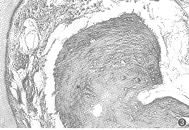

图1 BMP/GTR组:根分叉区牙周新附着形成较为完全,可见NB:新生牙槽骨;NC:新生牙骨质;CT:新生结缔组织附着;M:近中 (HE ×40)

图2 BMP/GTR组:根方切迹处牙周组织再生完全,N:切迹;D:牙本质 (HE ×40)

图3 BMP/GTR组:切迹处牙周组织新附着 (Van Gieson ×200)

图4 GTR组:根分叉区牙周组织再生不完全 (HE ×40)